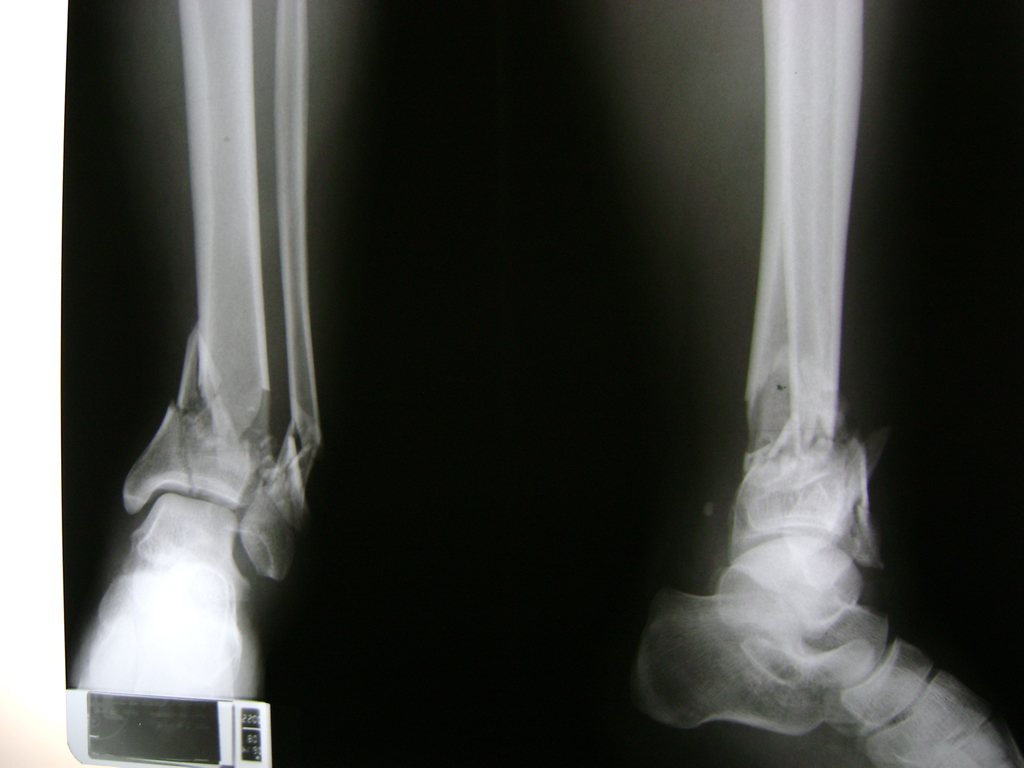

Una fractura de tobillo es la rotura de uno o más de los huesos del tobillo. Estas fracturas pueden ser:

- Los extremos de los huesos están desalineados entre sí (desplazados).

- La fractura se extiende hasta la articulación del tobillo (fractura intra-articular).

Cuando se necesita cirugía, es probable que esta implique el uso de clavijas de metal, tornillos o placas para sostener los huesos en su lugar mientras la fractura se consolida. Los elementos de soporte pueden ser temporales o permanentes.